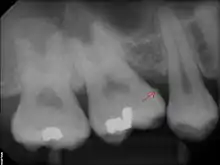

Sub-gingival calculus is composed almost entirely of two components: fossilized anaerobic bacteria whose biological composition has been replaced by calcium phosphate salts, and calcium phosphate salts that have joined the fossilized bacteria in calculus formations.[37][38] The initial attachment mechanism and the development of mature calculus formations are based on electrical charge.[39] Unlike calcium phosphate, the primary component of teeth, calcium phosphate salts exist as electrically unstable ions. The following minerals are detectable in calculus by X-ray diffraction: brushite (CaHPO4 · 2 H2O), octacalcium phosphate (Ca8H2(PO4)6 · 5 H2O), magnesium-containing whitlockite (Ca9(Mg,Fe)(PO4)6(PO3OH)), and carbonate-containing hydroxyapatite (approximately Ca5(PO4)3OH but containing some carbonate).[40]